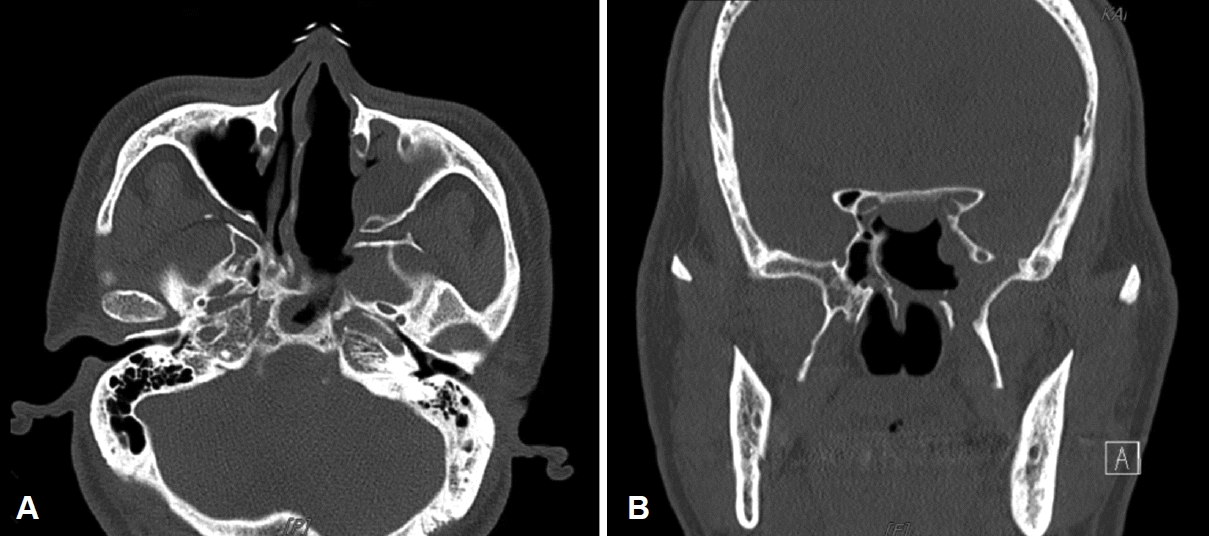

Fig. 2.

Preoperative contrast-enhanced CT revealed well-defined hypodense mass in the left nasal cavity. The lesion of the nasal cavity showed an expansive growth without bone invasion. Axial view (A), coronal view (B). Both sphenoid sinuses (asterisks), right vidian canal (arrow), and nasal cavity mass (arrowhead).